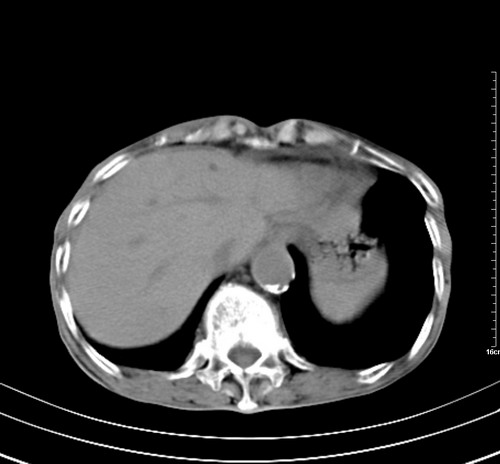

病人,女,79岁,主要因腹疼二月入院,彩超,肝,胆,脾,未见异常,胸透上消化道造影未见异常,化验白细胞增高,内科医生让做胸部ct检查,因为熟人多做了腹部(外科会诊考虑胆囊炎).现ct片如下请假各位战友.

1 气管旁、隆突下淋巴结明显肿大,肝左叶外侧段低密影,都考虑转移。

2 肝右后叶下段明显增大,片状低密影,但因各种伪影显示不佳,不排除病变。

后中纵隔团块影,伴气管、食道受压移位,首先考虑转移瘤,肝s5段低密度灶。建议增强检查,另外其结肠是否有问题请提供,右肺部分肺叶局限含气增多,考虑局限肺气肿。